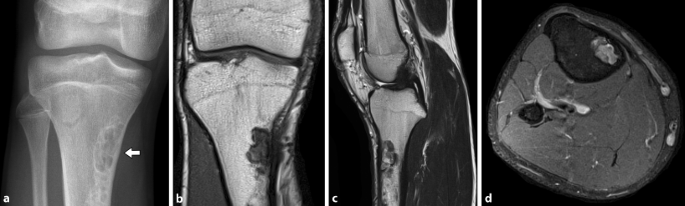

Figure 3 Die Pathologische Fraktur Aus Sicht Des Orthopaden Und Unfallchirurgen Springerlink